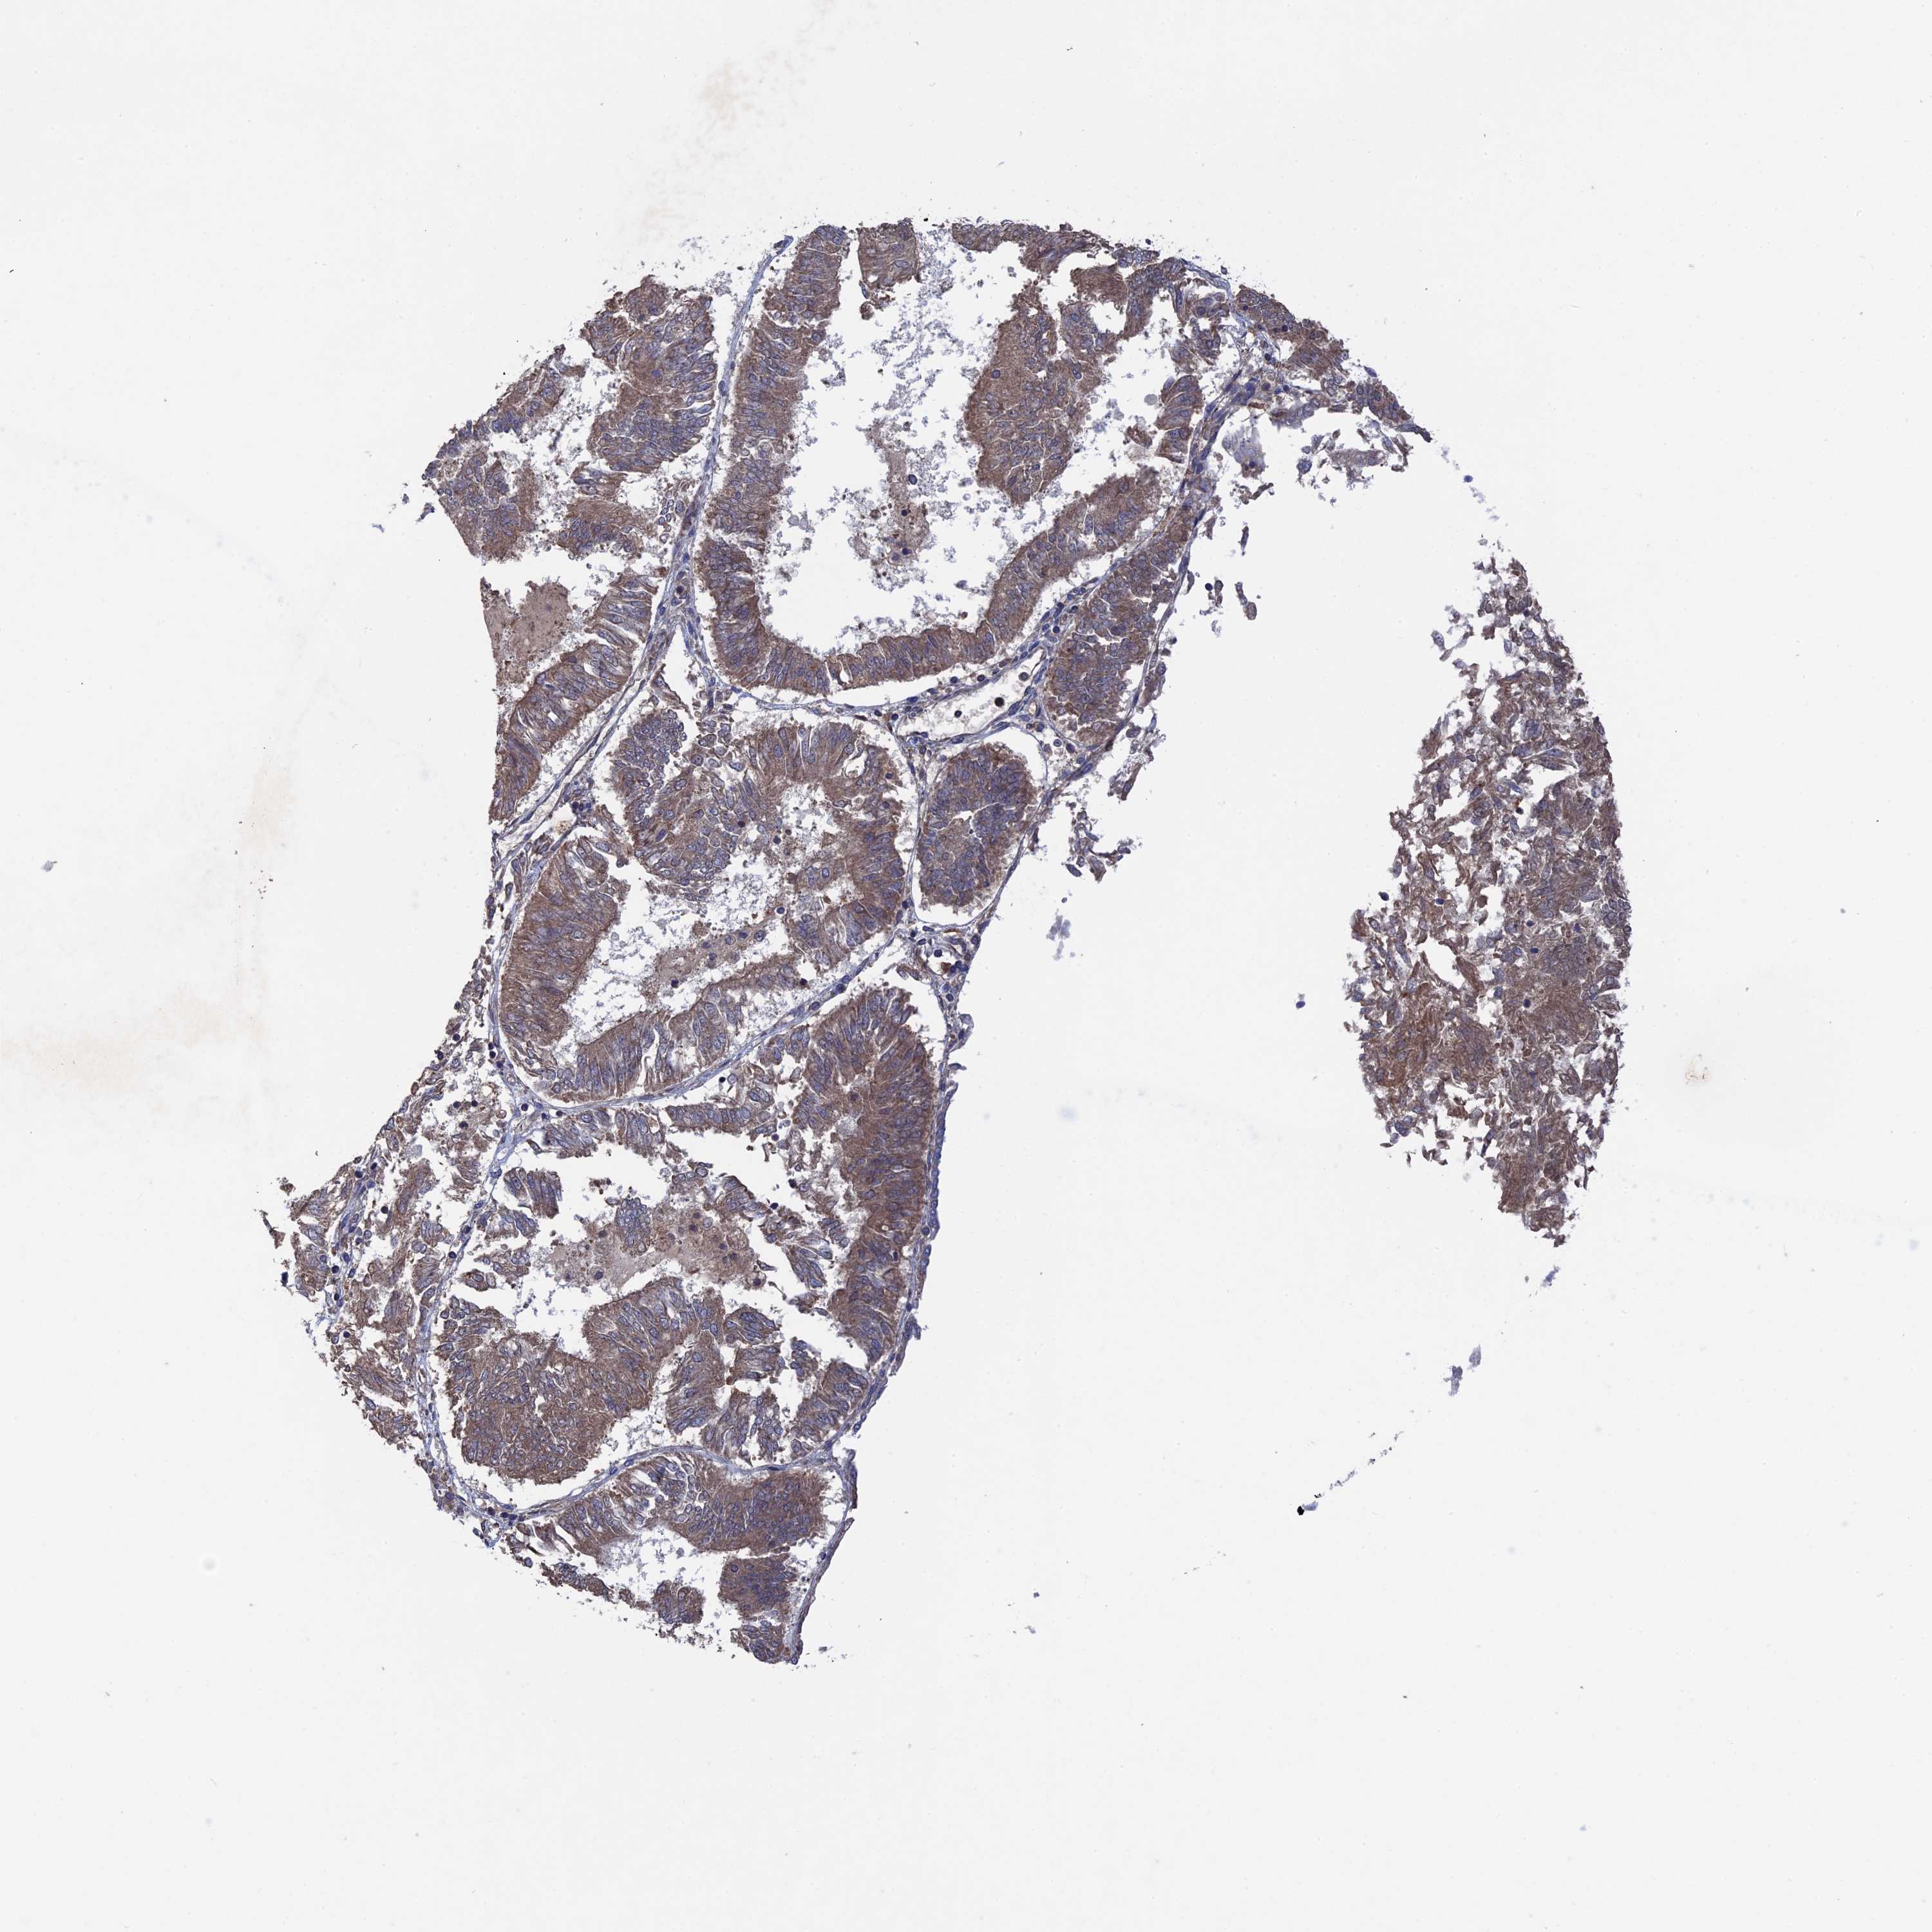

ENDOMETRIAL CANCER - Protein expressioni

A mouse-over function shows sample information and annotation data. Click on an image to view it in a full screen mode. Samples can be filtered based on level of antibody staining by selecting one or several of the following categories: high, medium, low and not detected. The assay and annotation is described here.

Note that samples used for immunohistochemistry by the Human Protein Atlas do not correspond to samples in the TCGA dataset.

Antibody stainingi

Antibody staining in the annotated cell types in the current human tissue is reported as not detected, low, medium, or high, based on conventional immunohistochemistry profiling in selected tissues. This score is based on the combination of the staining intensity and fraction of stained cells.

Each image is clickable and will lead to virtual microscopy that enables deeper exploration of all samples and also displays staining intensity scores, fraction scores and subcellular localization as well as patient and tissue information for each sample.

Antibody HPA041177

Staining

High

Medium

Low

Not detected

Intensity

Strong

Moderate

Weak

Negative

Quantity

>75%

75%-25%

<25%

None

Location

Nuclear

Cytoplasmic/membranous

Cytoplasmic/membranous,nuclear

Adenocarcinoma, NOS